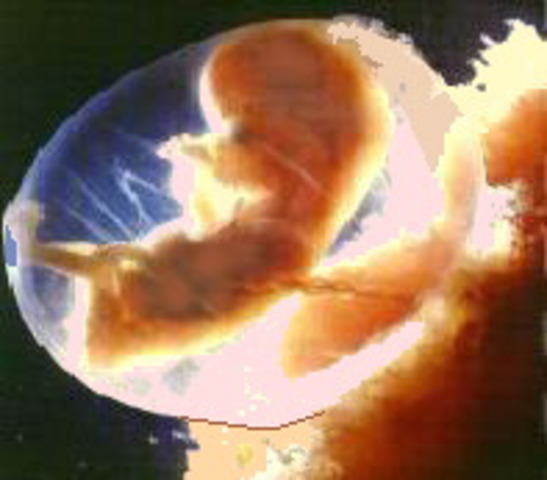

• week 9 of the fetal development

week 9 of the fetal development

the face and it's features are well formed. The head makes up nearly half of the fetus' size. Tooth buds appear.